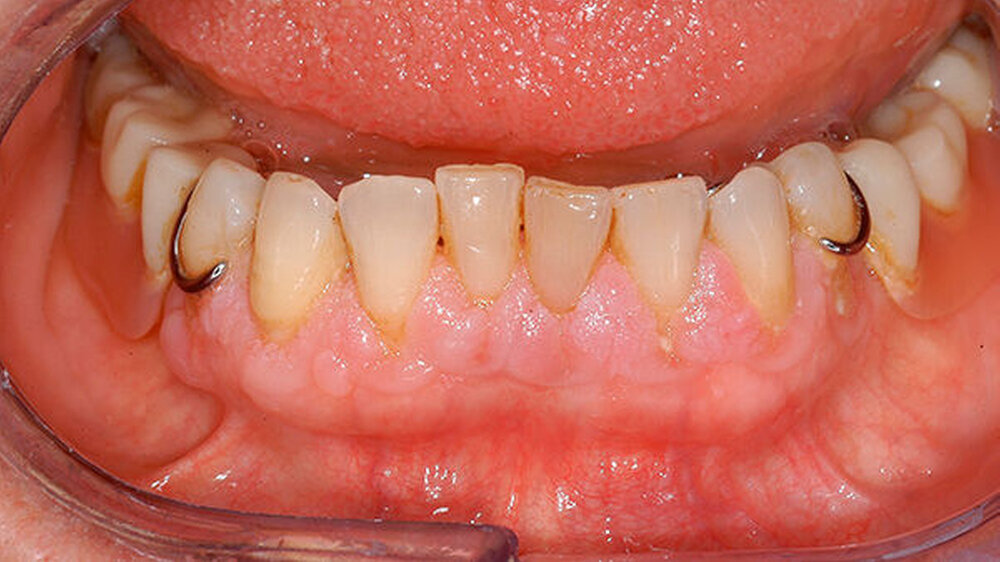

Aufgrund der schmerzhaften Gingivitis hatte die Patientin zudem Probleme mit der Nahrungsaufnahme. In der Panoramaschichtaufnahme (Abbildung 2) zeigt sich neben einem impaktierten Eckzahn ein Furkationsbefall der Molaren mit Konkrementen sowie ein altersentsprechender, generalisierter horizontaler Knochenabbau. Dennoch erschien uns das Volumen der Gingiva nach bereits erfolgter geschlossener Parodontaltherapie ungewöhnlich.